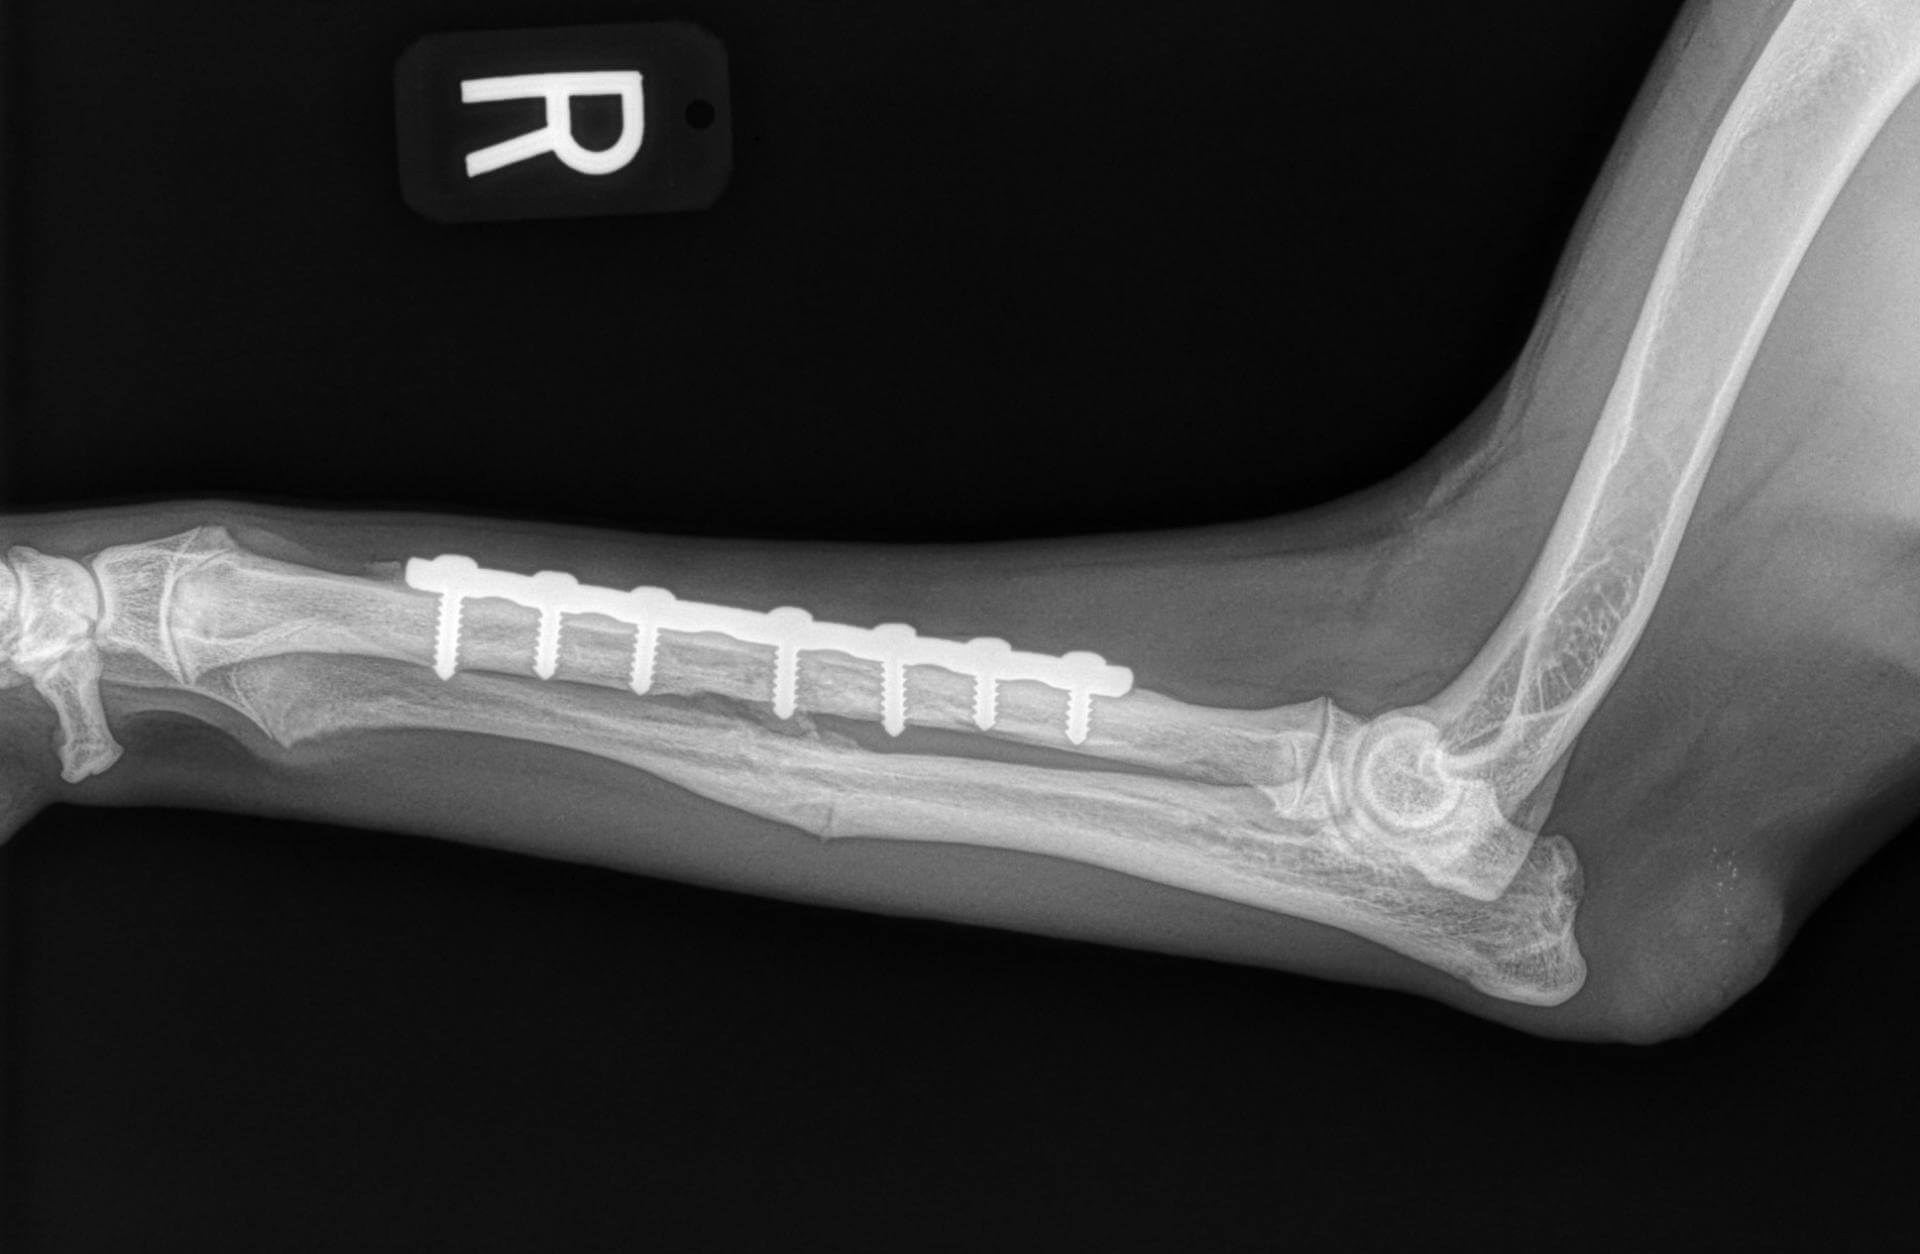

Dog leg fracture xray. Canine radius and ulna limb fracture radiograph

Dog X Ray. Radius and Ulna Fracture Repair with Plate and Screw in Dog Radius Ulna Fracture Dog Splint as mentioned earlier, distal radius/ulna fractures, especially those in small and toy breed dogs, addressed with external coaptation alone commonly result in malalignment or nonunion. — coaptation splints are commonly used for immobilization of simple transverse fractures of the radius, ulna, fibula, metacarpals, metatarsals,. this video show how to apply a splint that will be functional and. Radius Ulna Fracture Dog Splint.